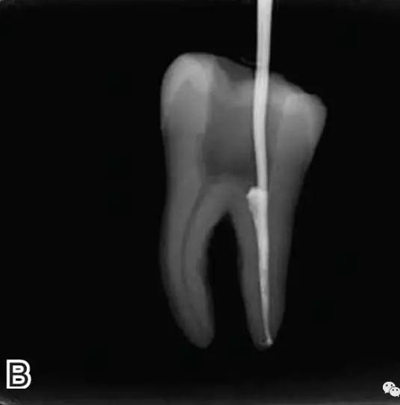

4、放置主尖及糊劑

將主尖的尖1/3 部分蘸一薄層根充糊劑,緩慢插入根管內(nèi),并左右旋轉(zhuǎn)主尖,以將根充糊劑均勻涂布于根管壁上,如圖4所示。

圖4 放置主尖及糊劑,A.放置主尖及糊劑 B.X線片下示主尖及糊劑的放置